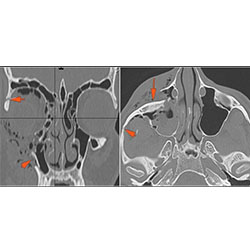

Right Temporal Bone

The external auditory canal shows abnormal soft tissue thickening.

The roof of the mastoid and/or middle ear is fractured.

A possible meningocele and/or encephalocele or CSF leak is present.

The ossicles, in particular the incus long process, the incudostapedial joint and stapes are fractured or dislocated.

The facial canal including the labyrinthine, tympanic and descending portions and nerve are fractured.

The inner ear including the lateral semicircular canals, vestibule and/or cochlea is fractured or otherwise abnormal.

Left Temporal Bone